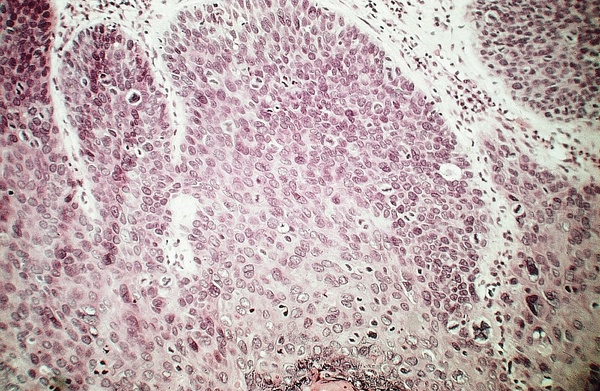

cervix - Infiltrating squamous cell carcinoma - Niche with asymmetric division (see high power 01120001.jpg) Niche surrounded by support cells with one self-renewal daughter cell (arrow) consisting of spheres and one differentiated tumor cell. (Infiltrating squamous cell carcinoma of uterine cervix [2]) |